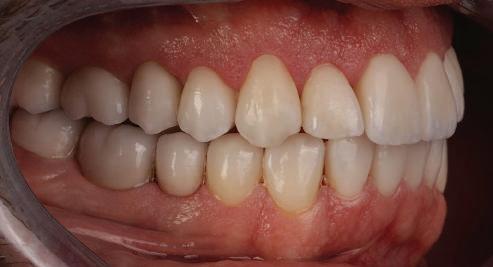

планта бе поставена временна коронка (фиг. 10 и 11), докато бъде изготвена окончателна та. Бе постигнат отличен кра ен резултат. Меките тъка ни около импланта напълно заздравяха, което доприне се за перфектната хармония между бяла и розова естетика (фиг. 12–15).

Dental Tribune Bulgarian Edition / октомври 2022 г.18 воначалния план. Тези пробле ми бяха адресирани чрез допъл нителна поръчка на алайнери с торк контрол и зададено екст рудиране на задните зъби с цел установяване на добри оклузал ни контакти в дисталните об ласти, като бяха предвидени и оптимизирани атачмънти с контрол над корените за корекция на ангулацията на макси ларните резци (фиг. 8). Резултати от лечението Панорамната рентгено графия след ортодонтското лечение показа благоприятна паралелна позиция на съседни те зъби, подходяща за поставя не на имплант в областта на #22, както и конвергенция на ко рените на зъби #44 и 45 (фиг. 9), но преценихме, че няма да от деляме допълнително лечебно време за коригирането ѝ поради факта, че пациентката бе мно го доволна от постигнатия до момента резултат. След при ключване на лечението бяха постигнати отлични взаимо отношения клас I при мола рите и канините, а срединни

съвпадаха. Върху им